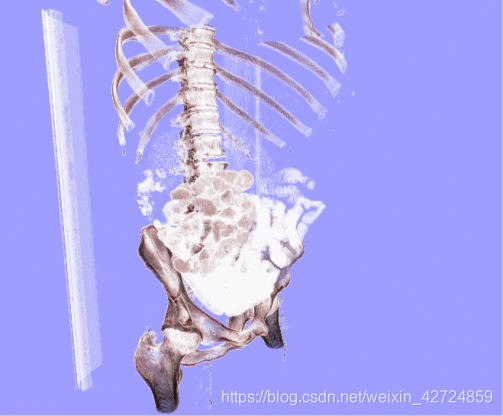

python-vtk做医学nii格式的三维重建

所以,我只得先去使用vtk-python实现对自己手上腹部nii数据的三维重建,继续往下

使用vtk-Python完成腹部nii数据的三维重建与人机交互